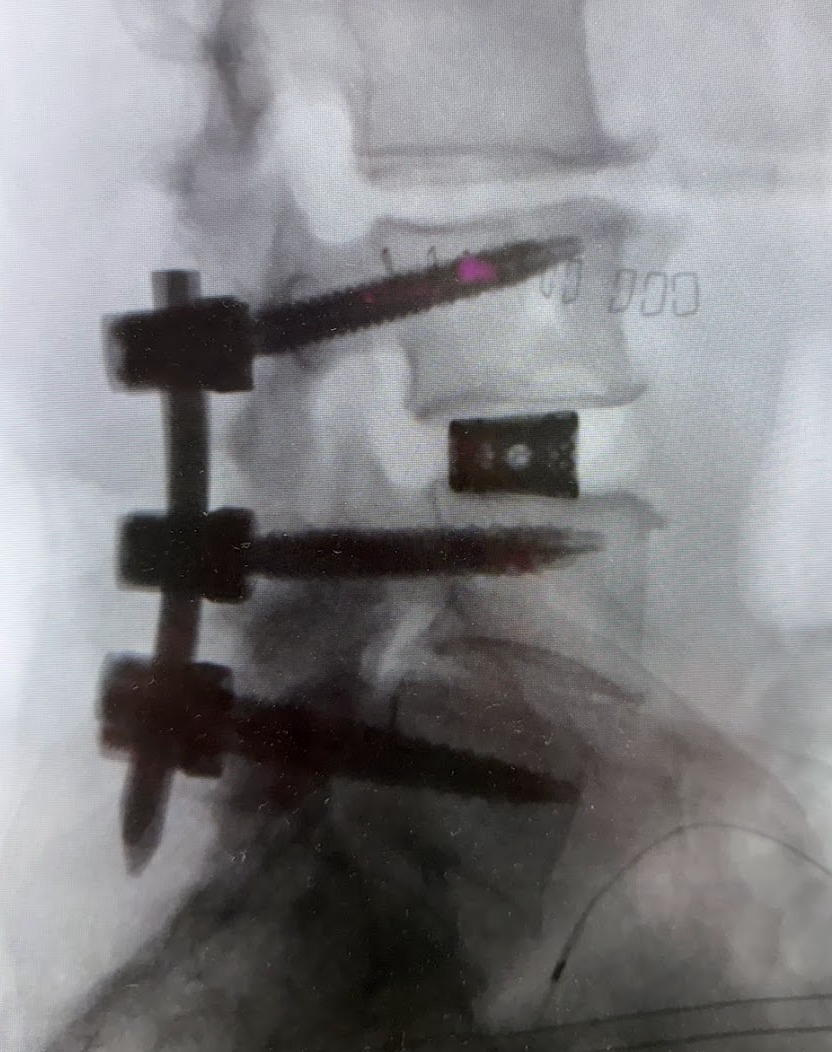

Ortopedia della Colonna Vertebrale